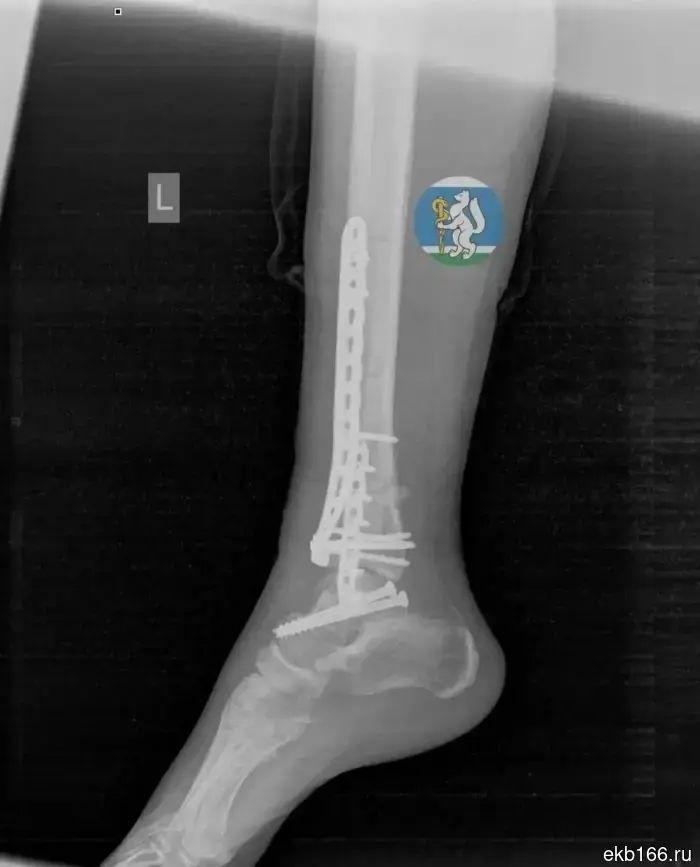

The woman was diagnosed with a traumatic brain injury, spinal damage, fractures of the pelvis and leg, as well as injuries to the chest and lungs. Doctors urgently brought her out of shock, stopped the bleeding, and performed a complex operation.

After that, the woman was in intensive care on a ventilator, and then underwent another procedure. Thanks to step-by-step treatment and early rehabilitation, she began to move again. A month later, the patient was discharged, and she is currently undergoing recovery.